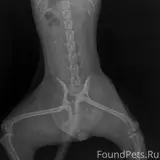

24.02.2026 убежала собака Мишель. 25.02.2026 найдена с многочисленными травмами и переломами. Перелом таза со смещением, ушибы органов мочевого пузыря. Требуется помощь в лечении и реабилитации. Контакт для помощи: +79995876731, карта Сбербанка, владелец: Наталья Сергеевна.